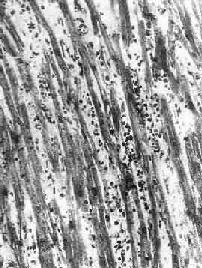

图8-41 病毒性心肌炎 心肌间质内有弥漫性淋巴细胞及组织细胞浸润

| 一、病毒性心肌炎病毒性心肌炎(viral myocarditis)颇为常见,是由亲心肌病毒引起的原发性心肌炎症,常累及心包,引起心包心肌炎。事实上,所谓特发性心肌炎极可能是因病毒感染引起。 【病因和发病机制】 可引起心肌炎的病毒种类颇多,其中最常见的是柯萨奇(Coxsackie)病毒、ECHO病毒(即人肠孤病毒)、风疹病毒、流行性感冒病毒、腮腺炎病毒等。由于在妊娠最初3个月内感染柯萨奇病毒和风疹病毒时可引起胎儿的先天性心脏畸形,因此,这两种病毒占有特别重要的地位。人类的心肌炎以柯萨奇病毒B组感染最为常见。一般而言,亲心肌病毒可直接破坏心肌细胞,但也可通过T细胞介导的免疫反应间接地破坏心肌细胞。由于此类病毒衣壳的糖蛋白分子结构与心肌细胞膜的糖蛋白相似,故在感染后,机体所产生的抗体(激活补体的抗体及中和病毒的抗体)既针对病毒,亦针对心肌细胞。因此,当细胞毒性T细胞被致敏后,即可破坏被病毒感染的心肌细胞。 【病变】 本病病变依患者年龄不同而有所不同。妊娠最初3个月的胎儿感染风疹病毒时,可引起心内膜下心肌的无反应性心肌细胞坏死。在妊娠后期,胎儿感染柯萨奇病毒时则可引起全心炎,大多伴有心骨膜纤维弹性组织增生。初生儿的病毒性心肌炎可见到心肌细胞坏死及粒细胞浸润。其后,代之以巨噬细胞、淋巴细胞、浆细胞浸润及肉芽组织形成(图8-41)。在成人,多累及心房后壁、室间隔及心尖区,有时可累及传导系统。镜下,主要病变为坏死性心肌炎。晚期,可见到明显的心肌间质纤维化,伴有代偿性心肌肥大及心腔扩张(充血性心肌病)。